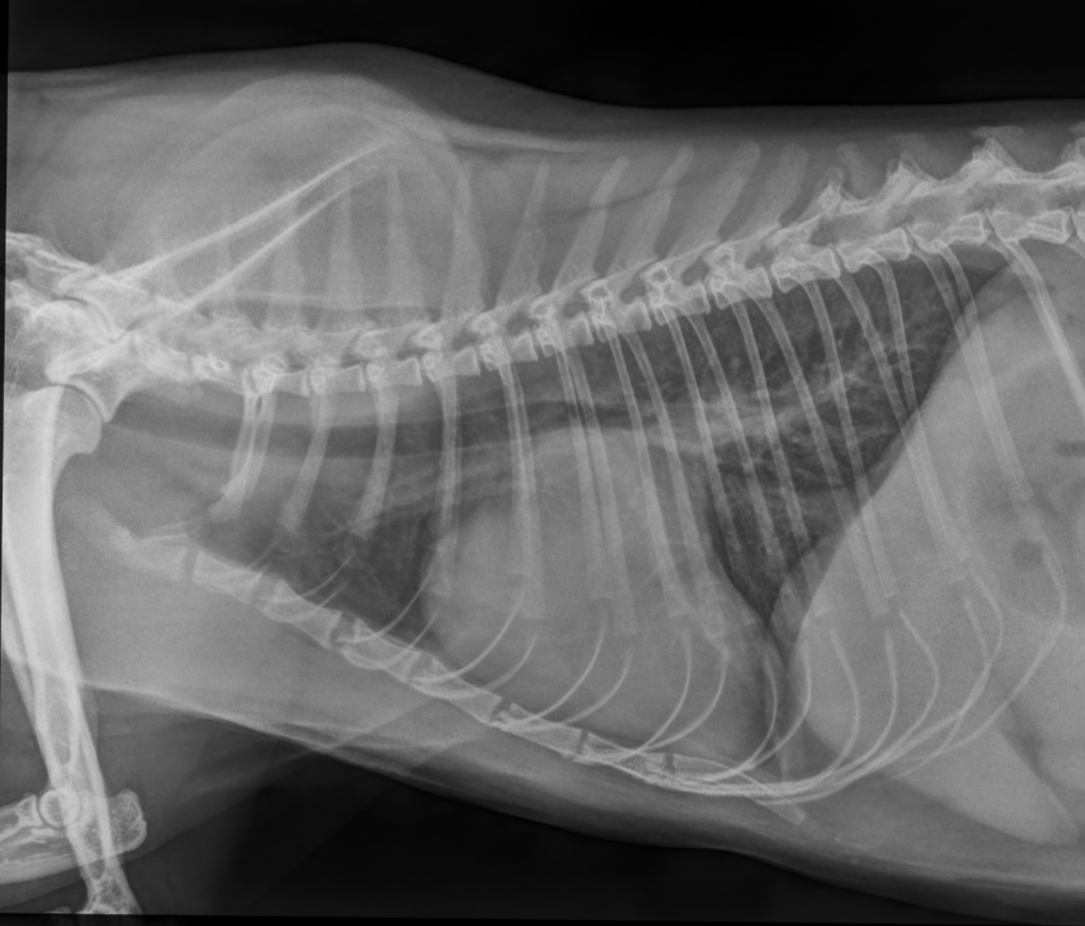

Ab einem gewissen Alter sollte daher ein regelmäßiger Check-up des Herzens obligatorisch sein. Neben dem Doppler- und B-Mode- Herzultraschall, gehören das EKG, das Röntgen zum manchmal auch Blutuntersuchungen zur vollständigen Abklärung der Herzgesundheit dazu. Frau Dr. Theresa Eulitz (Zusatzbezeichnung Kardiologie) ist unsere Spezialistin in Herzensangelegenheiten.